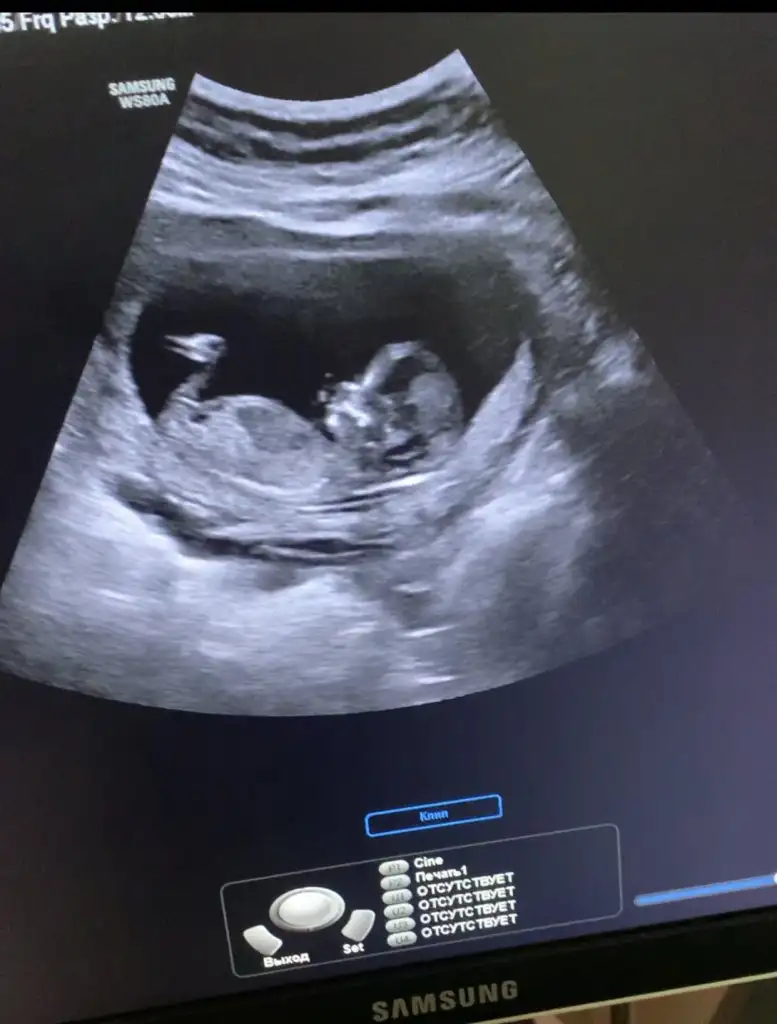

Merhaba. Rica etsem benim usmya tahmin yapar mısınız?

12+2 günlüktü burda. Karından detaylı ultrasondu.

Doktor benzetme yaptı ama kesin değil dedi.doktorla aynı olursa oyumu veririm

Kız sanki başka USG varsa paylaşın

Şimdiden teşkkür ederim

Eklentiler

• 65BDDEB2-67E8-469D-89E8-F1D5CA215B1C.webp

35,8 KB · Görüntüleme: 60

• 3F0F8959-971A-4368-8E36-B0678BC1EDFD.webp

13,8 KB · Görüntüleme: 48

• DBE55040-4A1B-4056-908E-1FABDFA1E512.webp

15,1 KB · Görüntüleme: 56